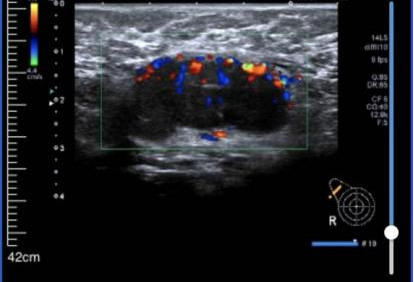

• 乳腺彩超:

1、右侧乳腺相当于9点钟方向距乳头约39.0mm腺体层内见范围约42.5*47.3*21.8mm不均质回声区,形态不规则,边界不清晰,内见丰富血流信号。其旁见大小约7.3*5.5mm低回声区,形态欠规则,边界欠清晰,内见强光点,内见少许血流信号。

2、右侧腋下见大小约31.0*15.8mm淋巴结影像,无正常淋巴门结构,形态尚规则,边界尚清晰,内见丰富血流信号。

超声提示:右侧乳腺实性肿块:BI-RADS 4C类;右侧腋下淋巴结肿大。

图1 乳腺彩超结果(2024-03-01)